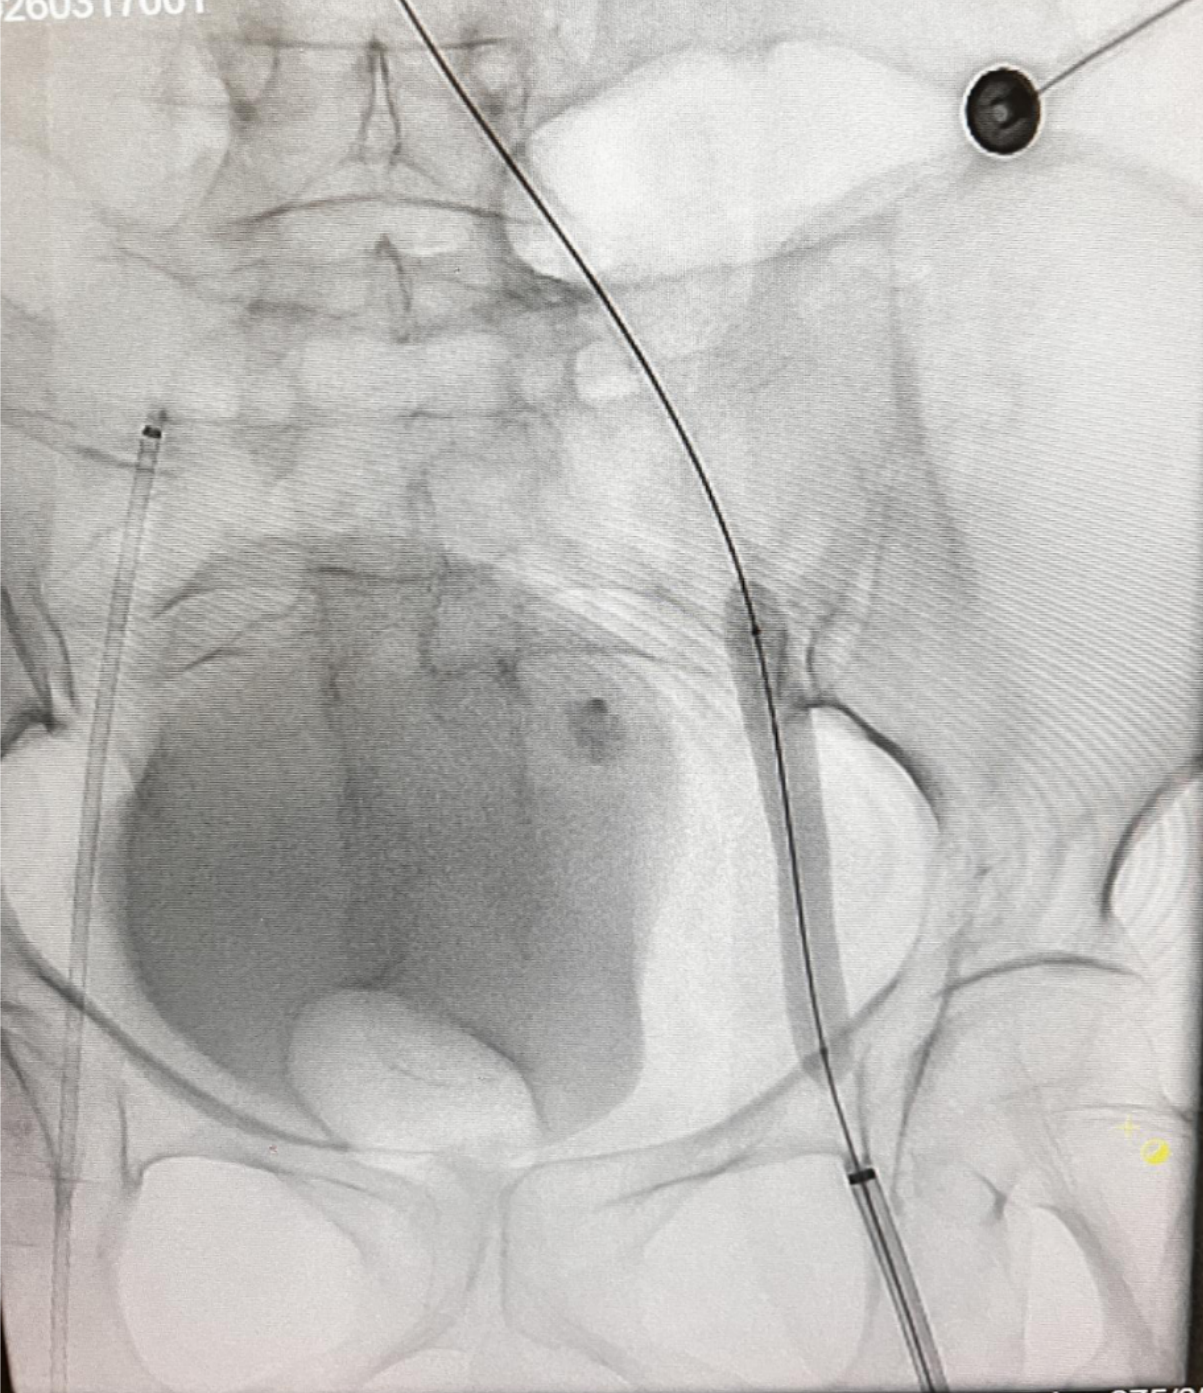

(图3:机械取栓(PMT)术中影像)

整台手术操作顺利,术中、术后患者生命体征平稳,血栓清除效果理想,患肢血流即刻恢复,下肢肿胀症状明显减轻。术后医院对患者予以规范抗凝治疗及严密病情监护,患者恢复进程顺利,各项临床指标趋于正常。